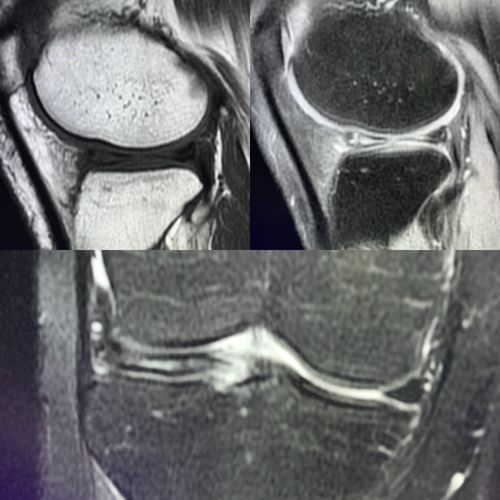

半月板损伤核磁共振图

半月板损伤核磁共振图,半月板损伤静养姿势

膝盖半月板损伤,拍了核磁,请医生朋友帮忙看看严重吗?

膝关节半月板损伤,磁共振几张图,请专家帮我看看!

半月板损伤磁共振图解

半月板核磁共振图解析

半月板磁共振图解

半月板3度撕裂共振图